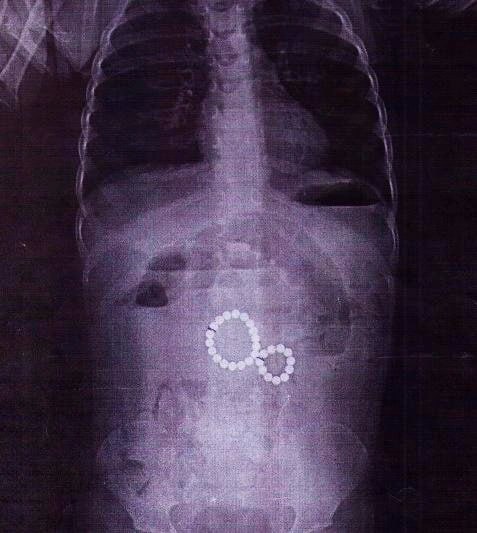

2-летняя девочка проглотила 29 магнитных шариков

Её прооперировали в Иркутской областной детской клинической больнице.

Рентген показал, что магниты соединились в «восьмёрку» и повредили кишечник, вызвав перитонит. Хирурги удалили все инородные тела и устранили осложнения. Сейчас малышка идёт на поправку.

❗️Врачи напоминают: даже два проглоченных магнита могут привести к тяжёлым последствиям. Родителям советуют не давать детям игрушки с магнитами, следить за мелкими предметами и при малейшем подозрении сразу обращаться к врачу. ИРСИТИ